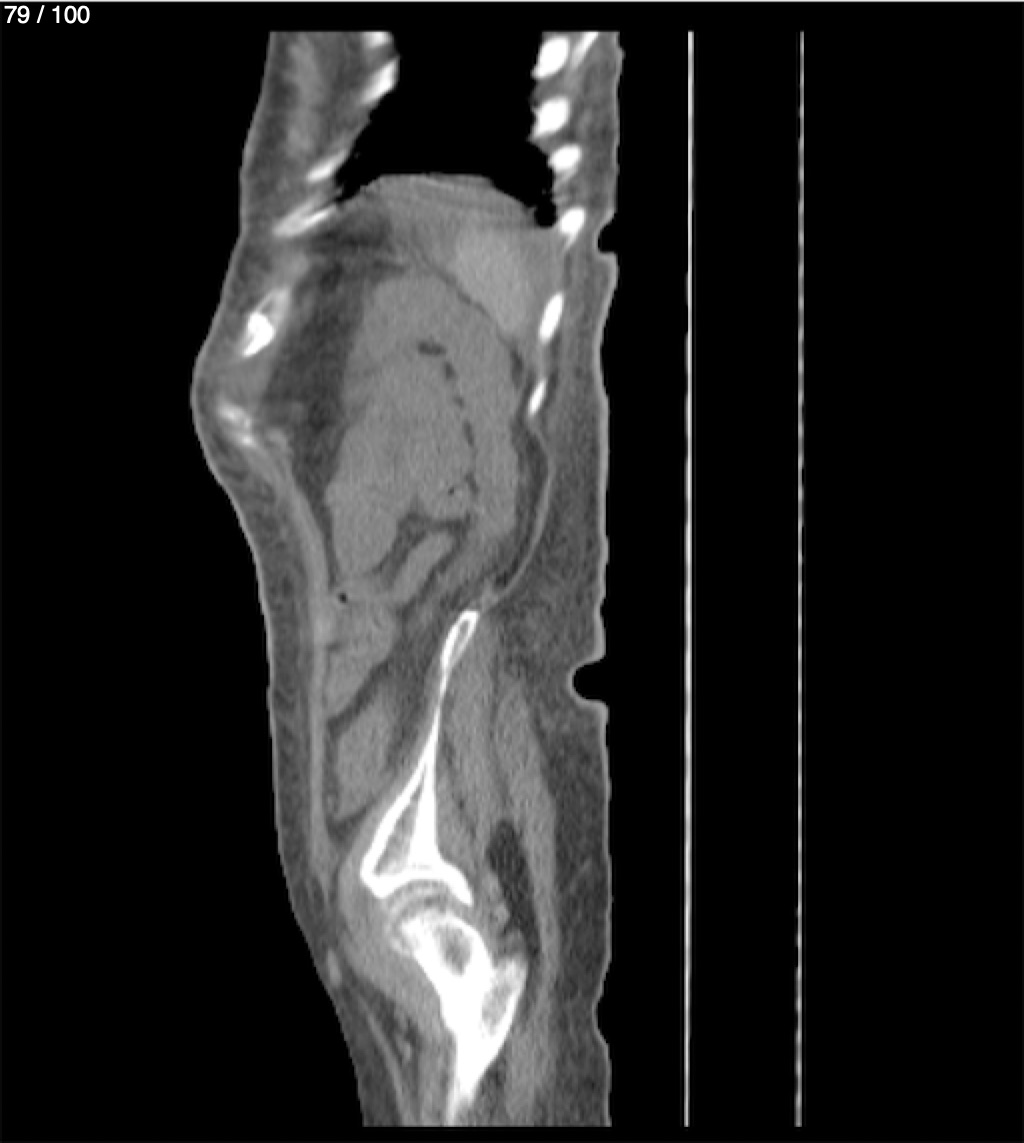

Hilda Geronimo Mendez 60A - T.C Abdomen Simple